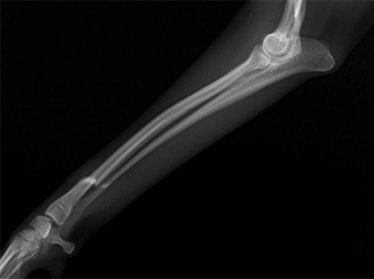

症例3:キルシュナーワイヤーのピンニングによる整復

ペルシャ猫 11ヶ月齢 雄

他院にて左大腿骨遠位の成長板骨折(salter-harrisⅠ型)が認められており、治療相談を目的として来院。当院にて、キルシュナーワイヤーを用いたピンニングにより骨折部位の整復を行いました。術後の経過は良好で、現在も経過観察中です。

術前レントゲン

術後レントゲン